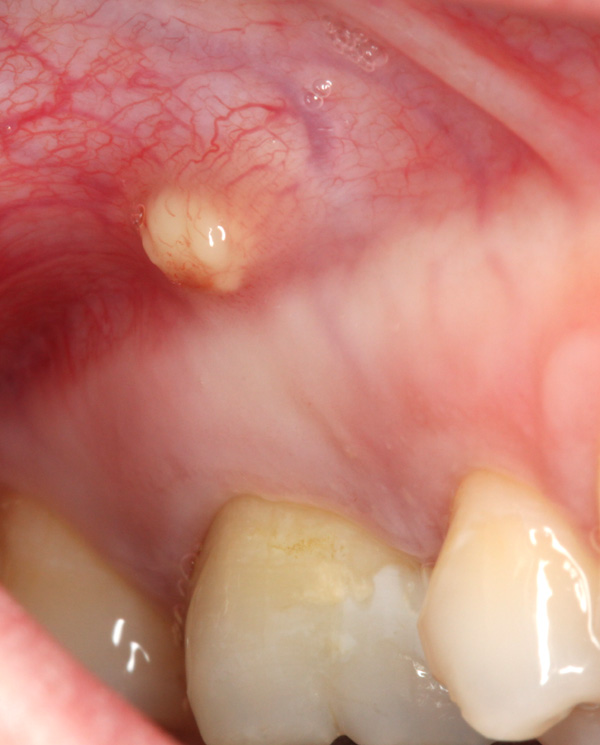

Zahn 16 bei einem Neuzugang reagierte nicht auf Kälte, hatte eine sehr große Amalgamfüllung und in der Höhe der Wurzelspitze zeigte sich eine mit Eiter gefüllte Fistel: